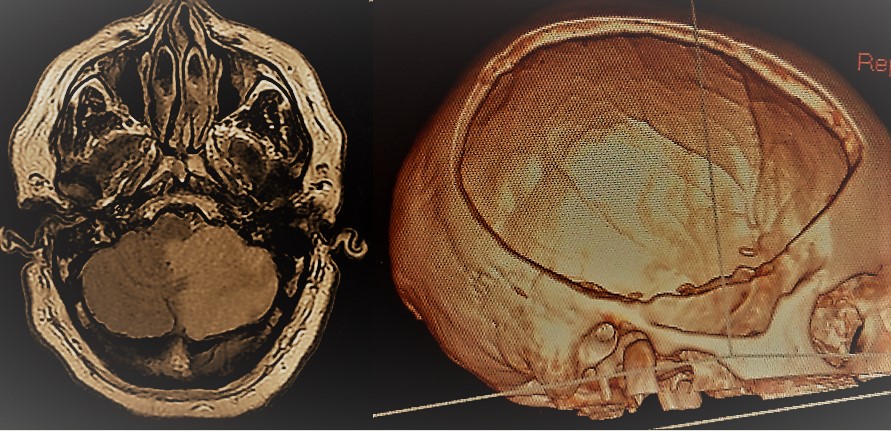

- Infarto cerebral maligno: Es un infarto cerebral de grandes dimensiones en el que la inflamación que tiene lugar en el parénquima afectado ejerce un efecto compresivo sobre el resto del cerebro, lo que puede conducir al coma y al fallecimiento en más de un 80% de los casos si no se pone remedio. El remedio en este caso viene dado por la craniectomía descompresiva que ha demostrado reducir de manera importante la mortalidad y en menor medida las secuelas neurológicas.